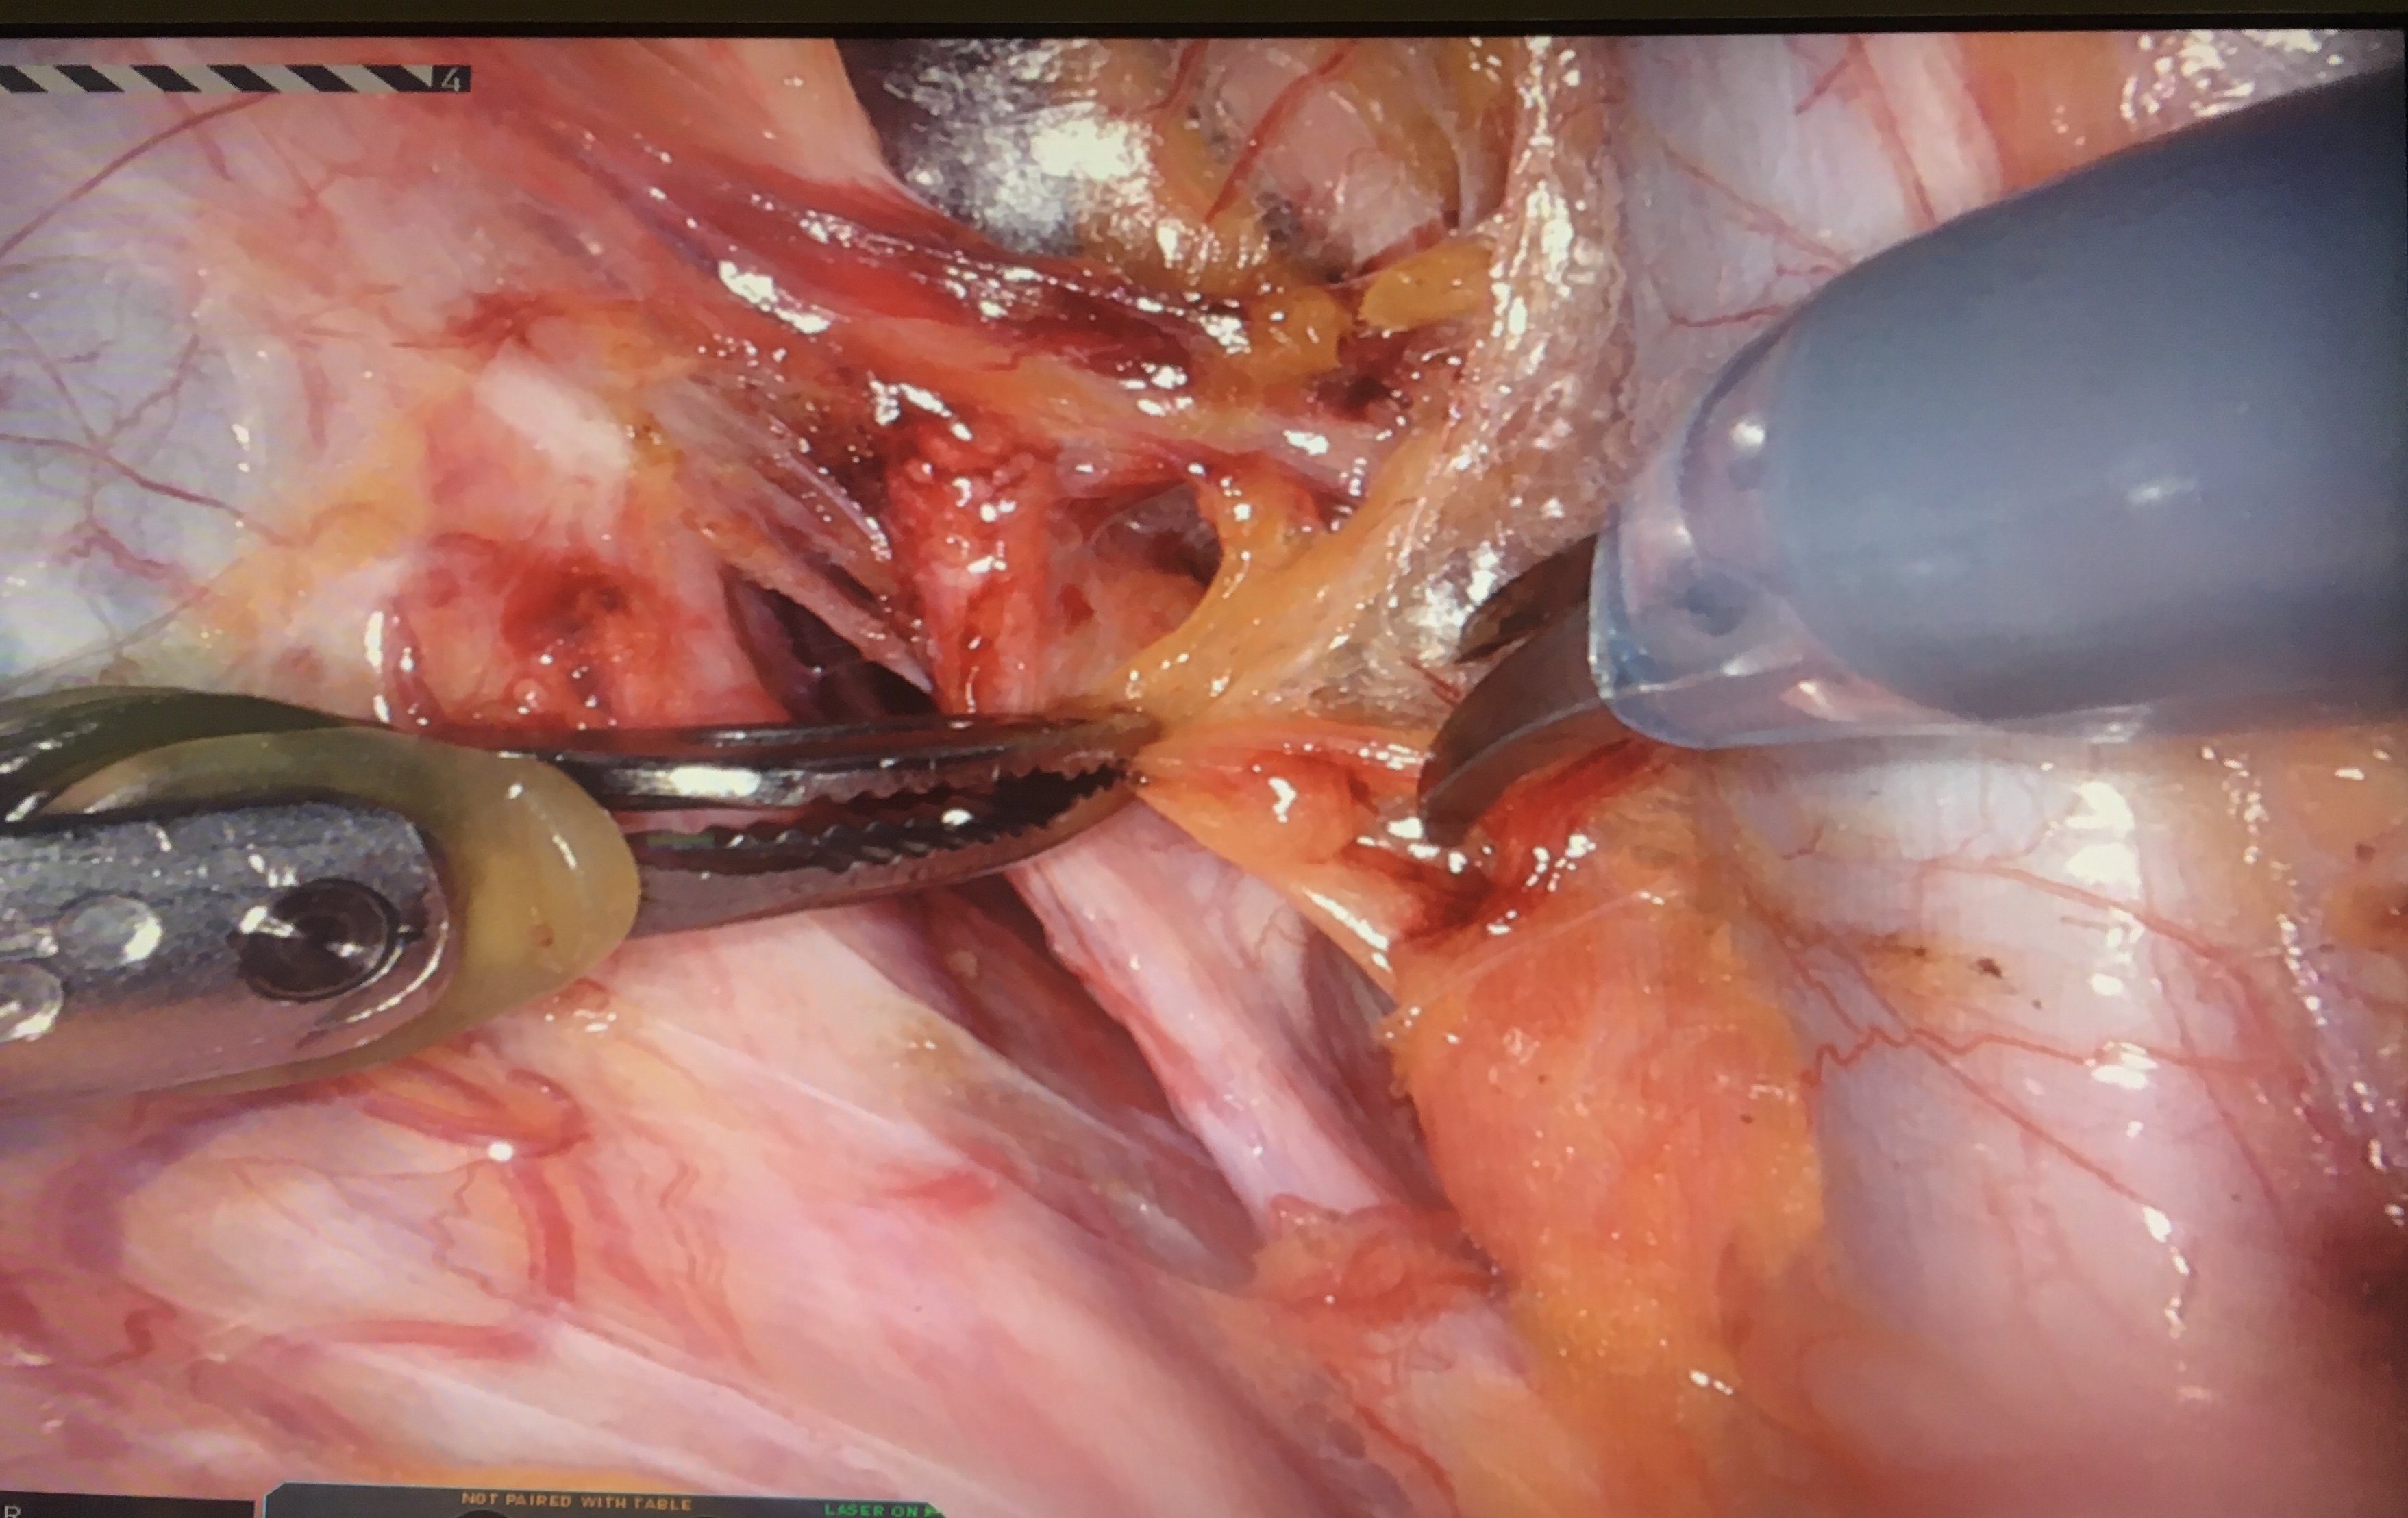

without dye3

Read more about "without dye3"... -